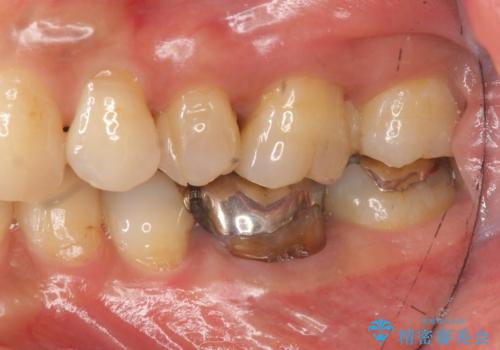

- 「笑った時に目立つ銀歯をきれいにしたい、皮膚科で金属アレルギーの可能性を指摘されたので金属を外したい。」

、とセラミック治療を希望され来院されました。

残っている歯を削らないよう、丁寧に除去したのち精密なジルコニアセラミッククラウンで再咬合構成を行っていきます。